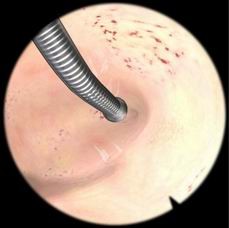

子宫内膜去除模块

可练习如何使用滚球电极,进行子宫内膜去除术的操作